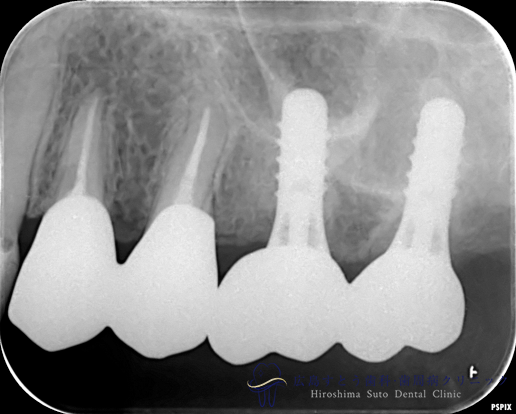

治療終了後のレントゲン写真

6ヶ月後のレントゲン写真

術後(インプラント治療後)

| 治療名 | GBR(骨再生誘導療法)、インプラント治療(2本分) |

|---|---|

| 治療説明 | 左上の奥歯に歯茎の腫れがあり、診査の結果歯根が破折しておりました。抜歯後はインプラント治療を希望されたため、抜歯後、失われた歯槽骨を増生するためにGBRを行い、インプラント治療を行いました。 |

| 治療回数・期間 | 約10ヶ月(歯周基本治療、抜歯、GBR、インプラント治療) |

| 副作用とリスク | 歯周外科後には一時的に術後に腫れや仏痛や出血が発現することがあります。 治癒の状態によって治療期間が長くかかる場合があります。 |

| 料金 | 104.5万円 |